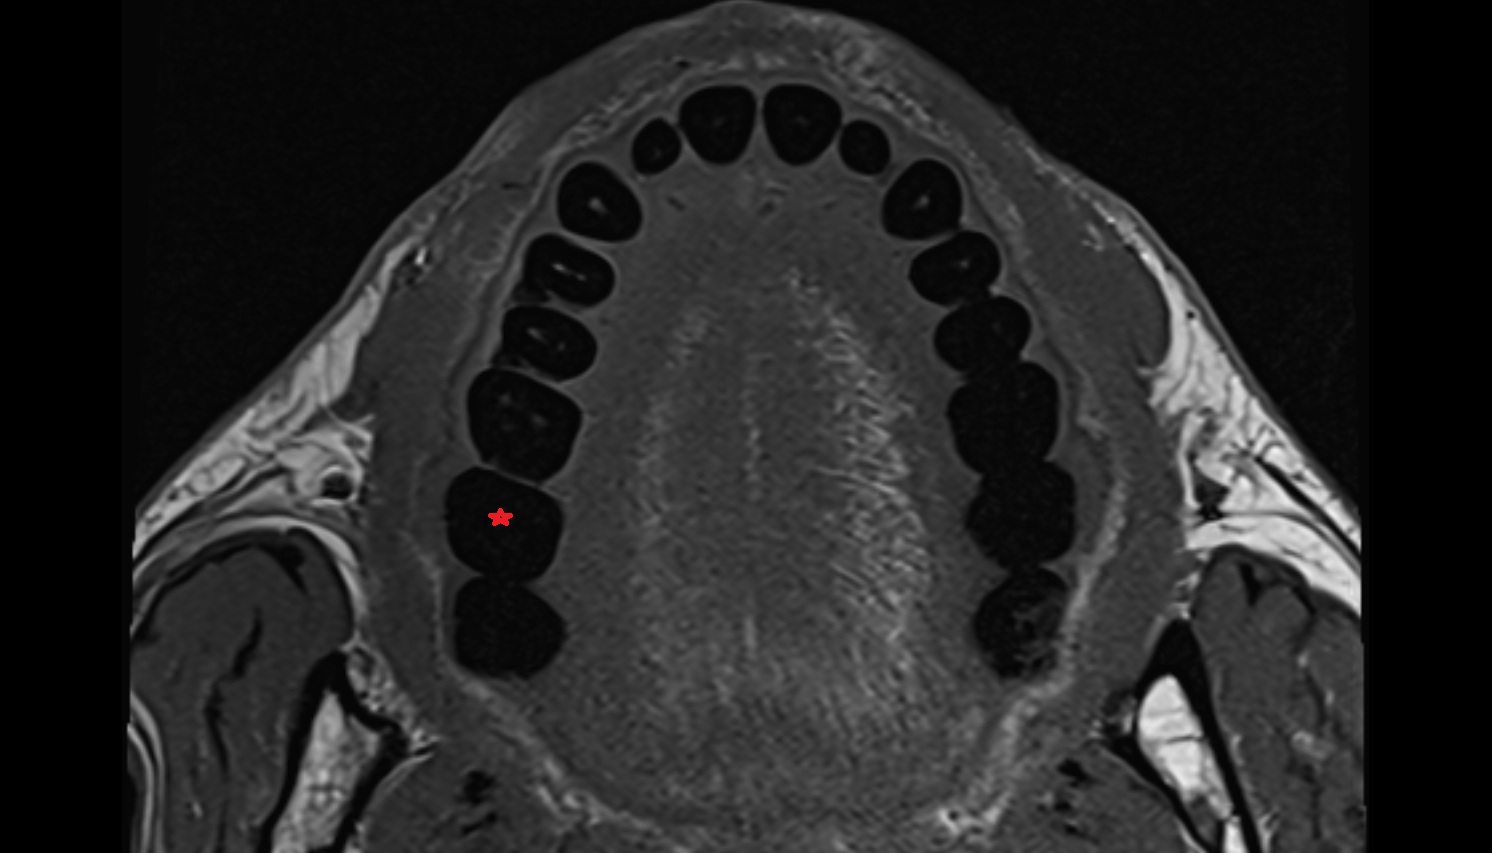

- Mandibular canal

- inferior alveolar artery

- Inferior alveolar nerve

- Mental nerve

- Mandibular foramen

- Root of lower molar tooth

- Lower molar apical foramen

- Upper premolar apical foramen

- Root of upper molar tooth

- Root canal of upper molar tooth

- Dental pulp of upper molar tooth

- Dental pulp of upper premolar tooth

- Enamel of lower molar tooth

- Mandibular nerve

- Dental pulp of lower molar tooth

- Root canal of lower premolar tooth

- Lower premolar apical foramen

- Dental branches of inferior alveolar artery, vein, & nerve

- Alveolar process of maxilla